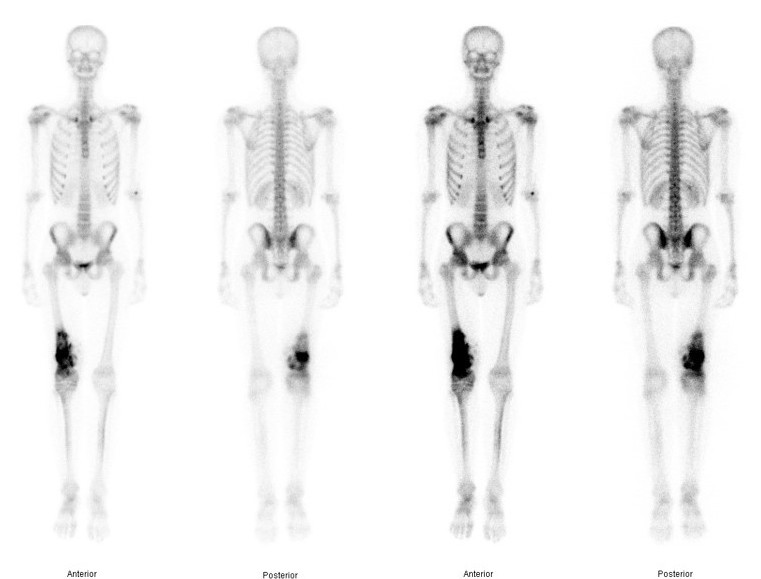

Bone Scan

1. Identify margins for resection / identify skip lesions

2. Identify metastatic disease

Bone scan with isolated disease

Bone scan metastasis